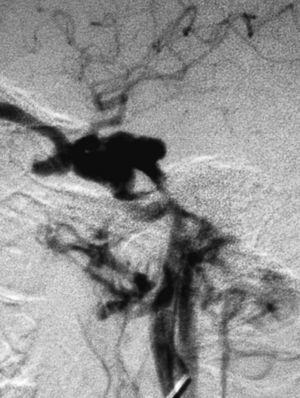

La vía de acceso venosa se empleó con éxito en 5 pacientes que se sometieron a embolizaciones de abordaje mixto, arterial y venoso, que en ocasiones es necesario para conseguir el cierre completo3. En 4 casos se usaron partículas y coils como material embolizante (fig. 5) y en otro adhesivo líquido y coils. Se alcanzó la mejoría completa en 2 casos y en 3 parcial.

Fig. 5.--A) Arteriografía en la fase arterial, proyección lateral, con inyección de contraste en la arteria carótida interna (ACI) izquierda en una fístula carótido-cavernosa (FCC) dural tipo D; muestra los aportes arteriales desde ramas meningohipofisarias de la ACI a la fístula, con relleno del seno cavernoso izquierdo. B) Cateterización selectiva de los aportes arteriales de ramas durales de la arteria carótica externa (ACE) y embolización con partículas de polivinil alcohol (PVA) de 250-350 micras. C) Control arteriográfico con inyección de contraste en ACE, en fase arterial y proyección lateral tras la embolización transarterial con partículas. Se observa cierre de los aportes durales desde ramas de la ACE. D) Embolización transvenosa del seno cavernoso con coils; la imagen de control con inyección selectiva de contraste en ACI, en fase arterial y proyección lateral, muestra un importante cierre de los aportes meningohipofisarios a la fístula.